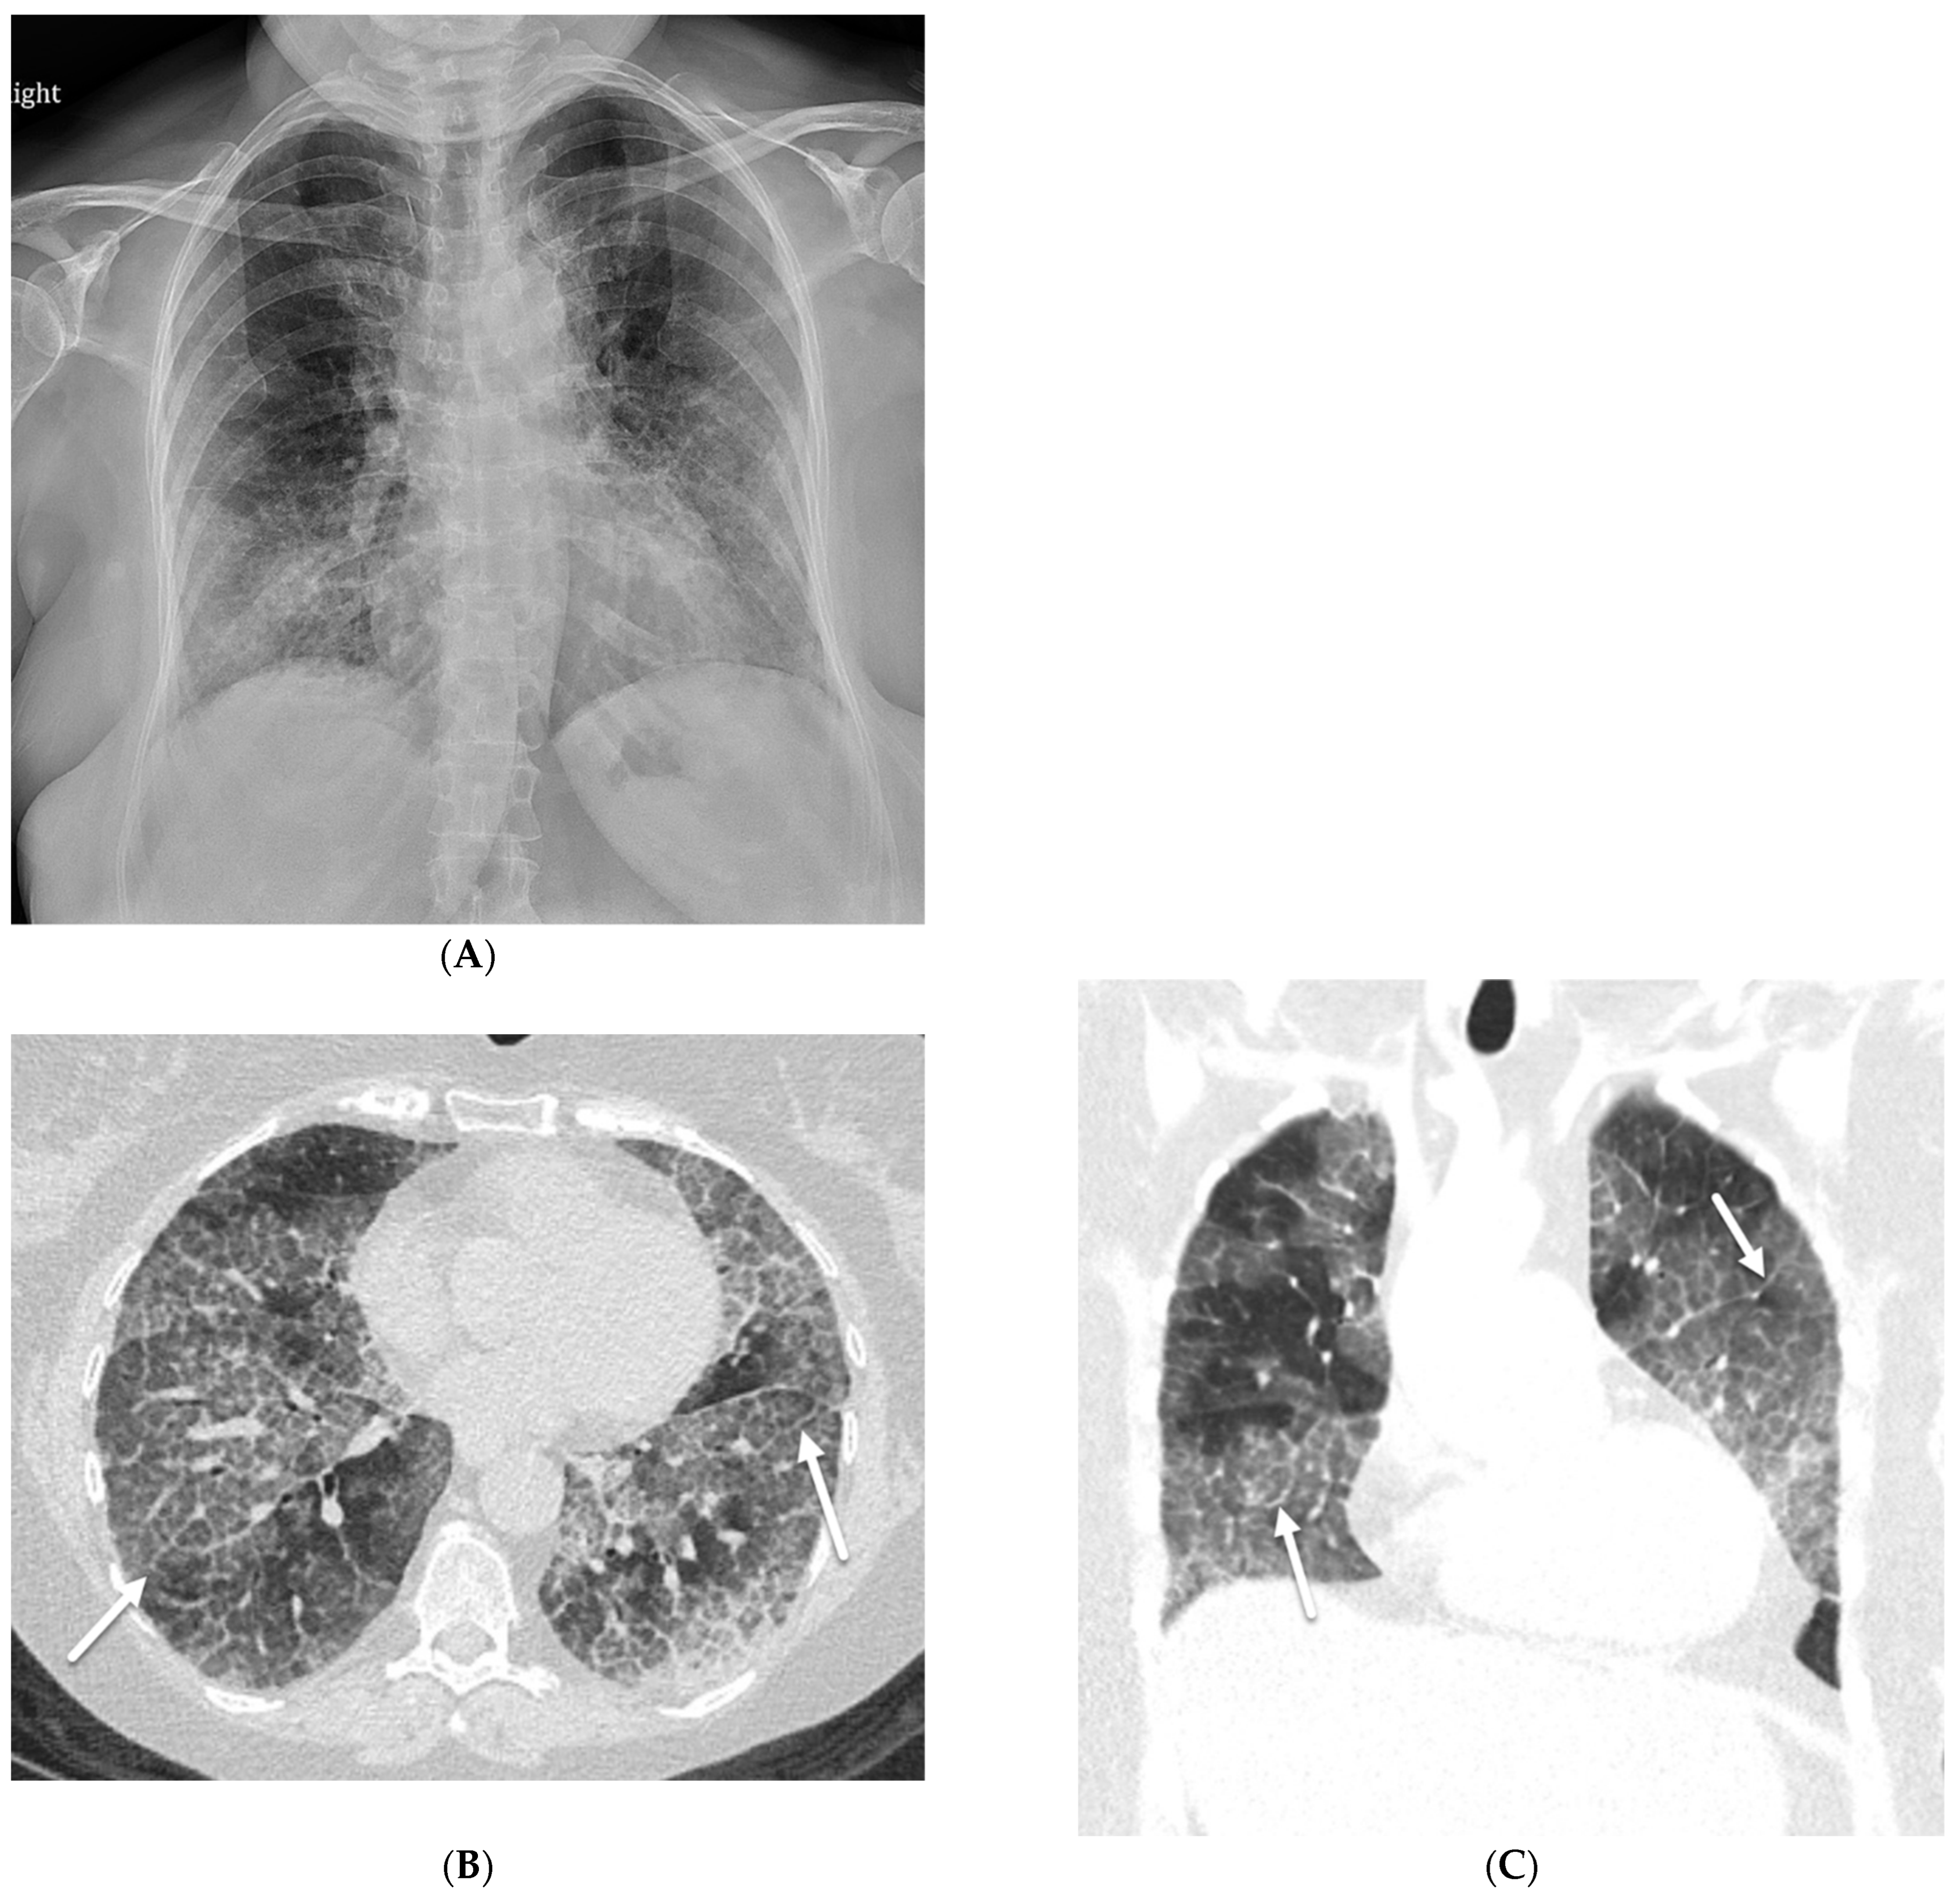

7.7. Coatomer Subunit Alpha (COPA) Syndrome

- Nguyen, H.N.; Salman, R.; Vogel, T.P.; Silva-Carmona, M.; DeGuzman, M.; Guillerman, R.P. Imaging findings of COPA Syndrome. Pediatr. Radiol. 2023, 53, 844–853. [Google Scholar] [CrossRef] [PubMed]